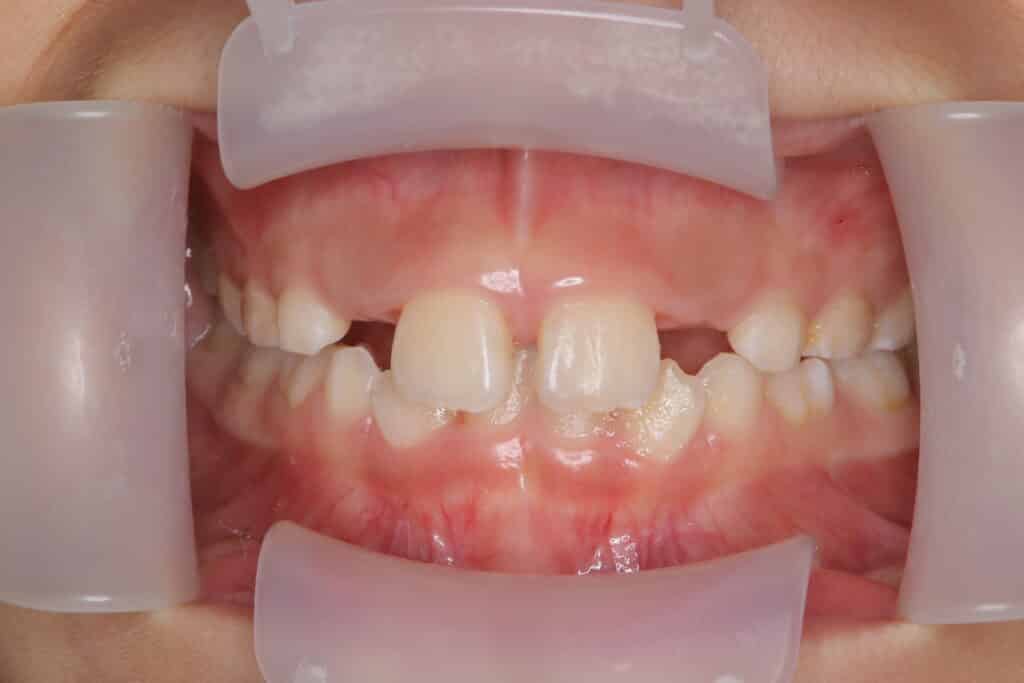

症例写真:治療前(7歳1か月)

小学生男児の歯並びが悪いことを親御様が気にされて歯並び相談に来院されました。

下の前歯のデコボコや歯と歯の間に隙間があるすきっ歯の症状も見られました。

診断の結果、歯の大きさに対して顎の骨が小さく、永久歯がデコボコに生えてくると予測されるため、取り外しのできるインビザラインによる矯正治療を開始しました。